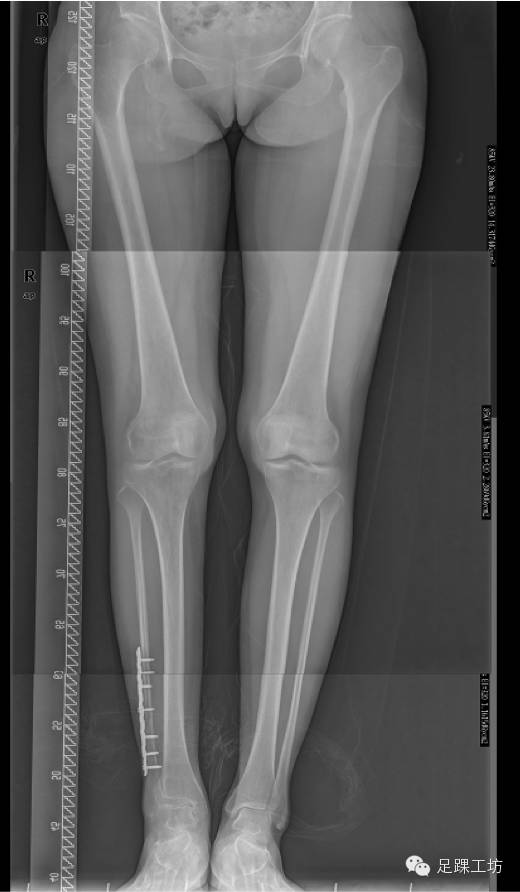

下肢全长X线